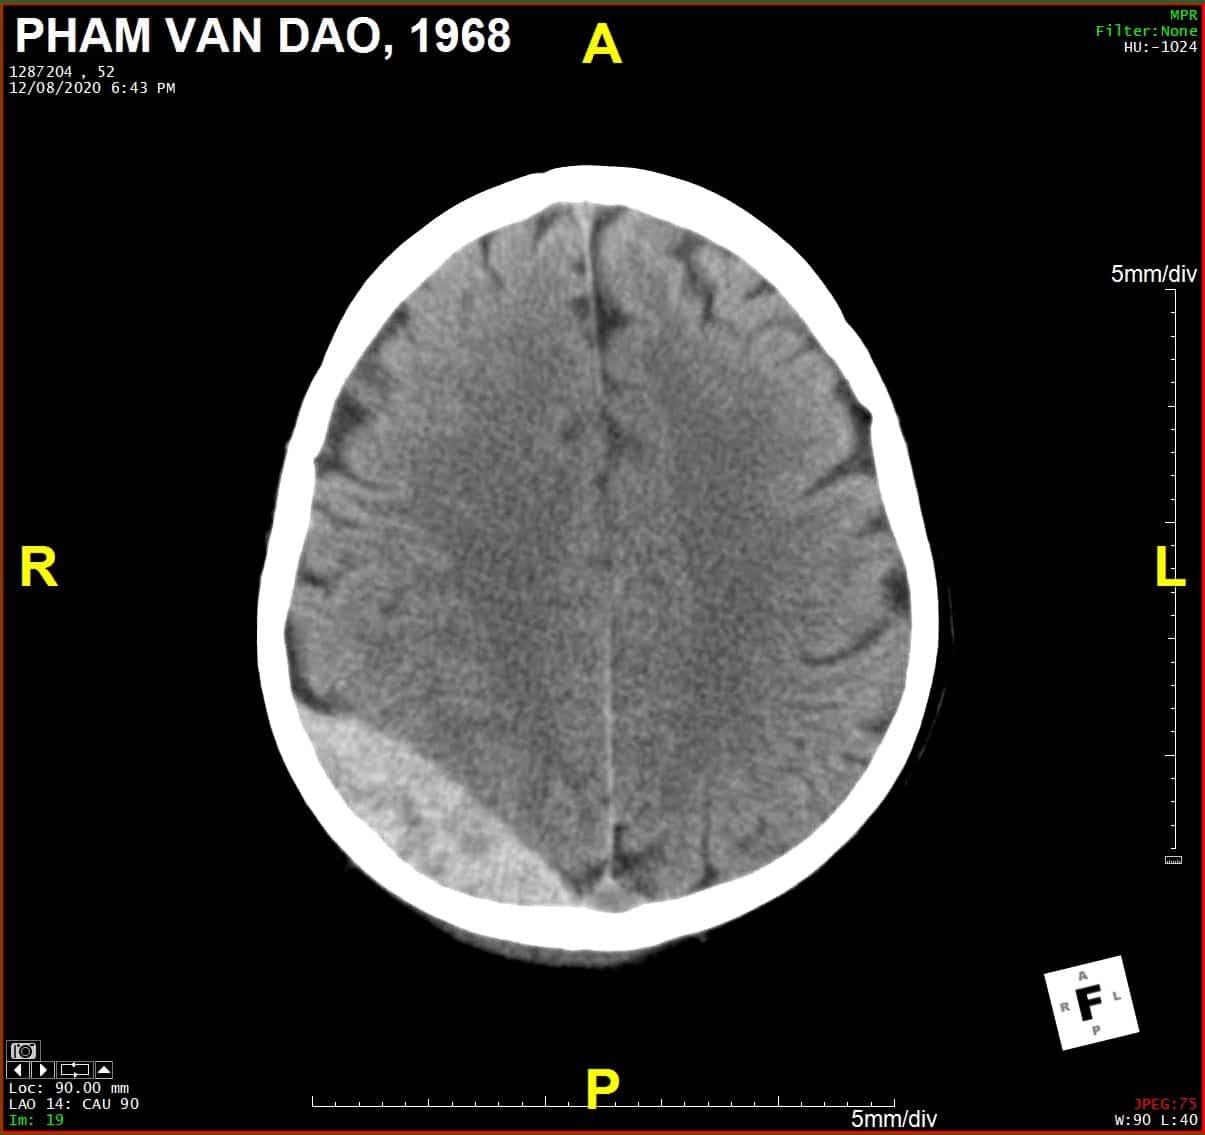

Chấn thương sọ - Ảnh 4

# Tụ máu ngoài màng cứng vùng chẩm phải / Vỡ xương chẩm phải: đường vỡ thẳng (Linear fracture) không thấy rõ trên hướng cắt Axial => quan sát rõ trên hướng cắt Coronal và Sagittal.